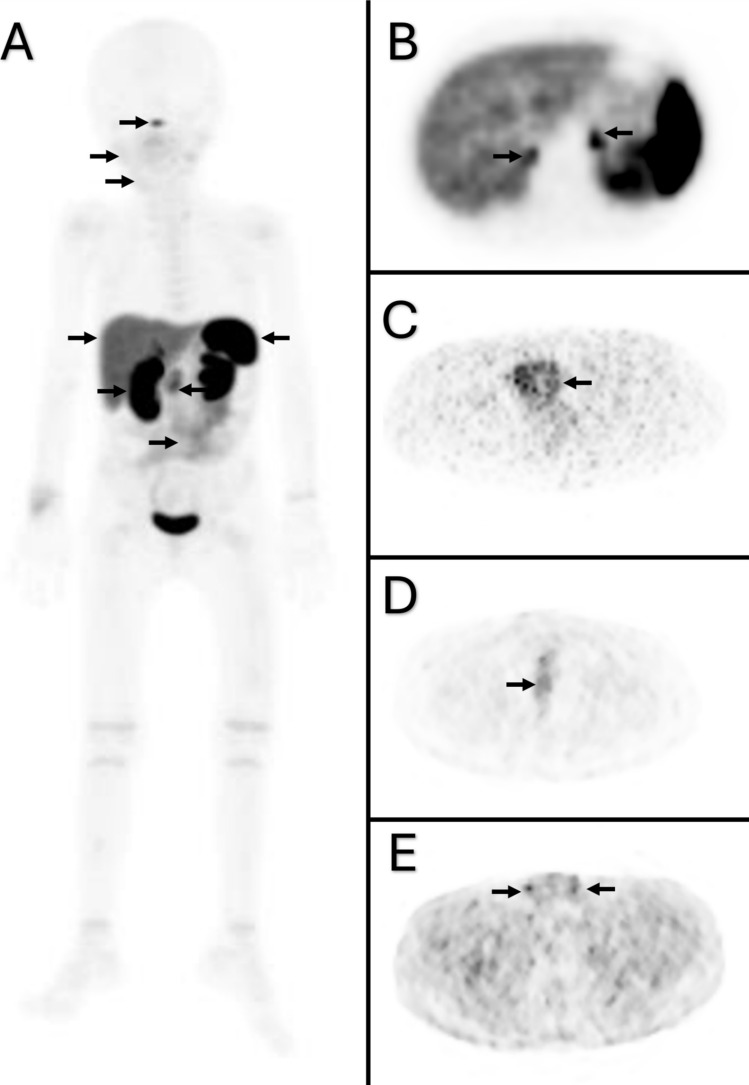

Somatostatin receptors (SSTRs) are G protein-coupled transmembrane receptors that serve as a specific molecular target for a number of radiopharmaceuticals utilized for the imaging of neuroendocrine tumors (NETs). 68Ga-DOTA-TATE is a somatostatin analog that demonstrates a high affinity for SSTR2. Pediatric malignancies, such as neuroblastoma, pheochromocytoma, and paraganglioma, have been shown to express SSTR2, and 68Ga-DOTA-TATE is currently being used to evaluate these pediatric neoplasms. We aimed to analyze the distribution pattern of 68Ga-DOTA-TATE based on age and location in pediatric patients.

We retrospectively analyzed 247 consecutive 68Ga-DOTA-TATE whole-body PET/CT scans performed in our department from May 2015 to April 2024 in pediatric patients with known or suspected neuroblastoma, neuroendocrine malignancy, pheochromocytoma, and paraganglioma. 93 subjects were included in this study who were disease-free at the time of imaging and had no tracer-avid lesion on 68Ga-DOTA-TATE PET/CT. The patients were divided into four groups according to age: infant (0–2 years), pre-school (3–6 years), school (7–12 years), and adolescent (13–18 years). A comparison of the SUV values of each organ across age groups was performed.

The highest levels of physiological uptake were observed in the spleen across all age groups, except for infants, who demonstrated the highest SUV values in the kidneys. 68Ga-DOTA-TATE uptake in the parotid glands, submandibular glands, thyroid gland, thymus, liver, spleen, adrenal glands, stomach, intestines, uterus, prostate, and testes demonstrated a statistically significant increase in the adolescent age group. In contrast to all internal organs, the lowest SUV max values were observed for all growth plates within the adolescent age group.

This study presents the bio-distribution pattern of 68Ga-DOTA-TATE in pediatric patients, according to age and location. The ranges of the SUVmax and SUVmean values of 68Ga-DOTA-TATE obtained in the various organs are of paramount importance for accurately diagnosing malignancy in 68Ga-DOTA-TATE PET/CT studies.